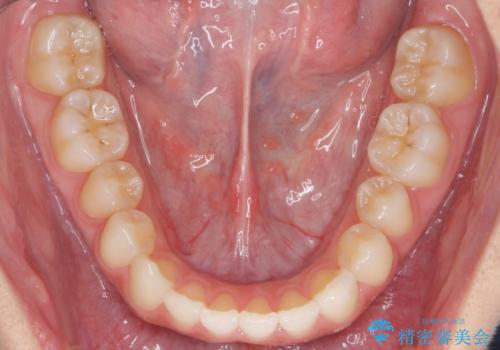

- 前歯の並びを主訴に来院。

前歯が出ており、また、左上の側切歯が1本生まれつき少ない状態でした。

また、右の奥歯の関係も上が前にある状態で大きくずれていました。

今回は左右とも1歯対2歯の関係であるため、それは変えずに前歯を可及的にひっこめて足りない部分をブリッジで補う治療としました。

奥歯の関係を完全に1級にするには右上の小臼歯の抜歯が必要でしたが、もともと左上の前歯が生まれつき少ないため今回は歯を抜かずに治療しています。